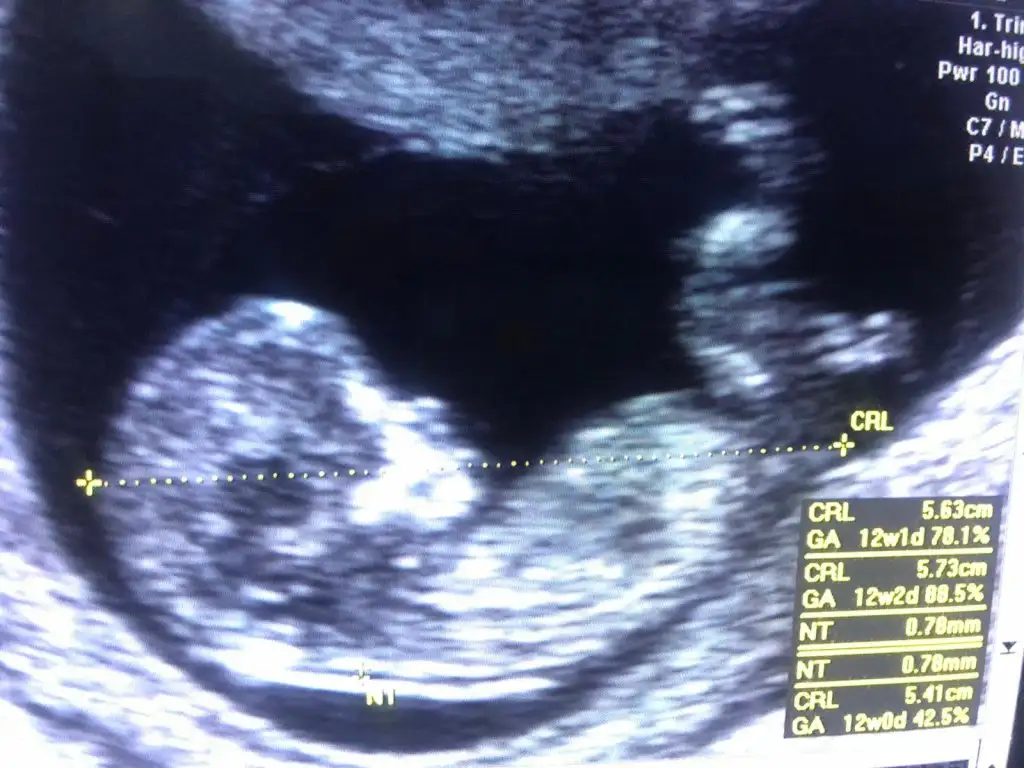

Kız gibi sankiKızlar 12+2 bana da bakarmısınız nuba göre cinsiyet nedir

12+3 haftalik benim bebegimide yorumlar misin?Ikra meyra

Alttaki bacak arasi görüntüsü

doktorum 1 ay sonra söylerim dedi merak ediyorum.. :)

videodan ss aldim